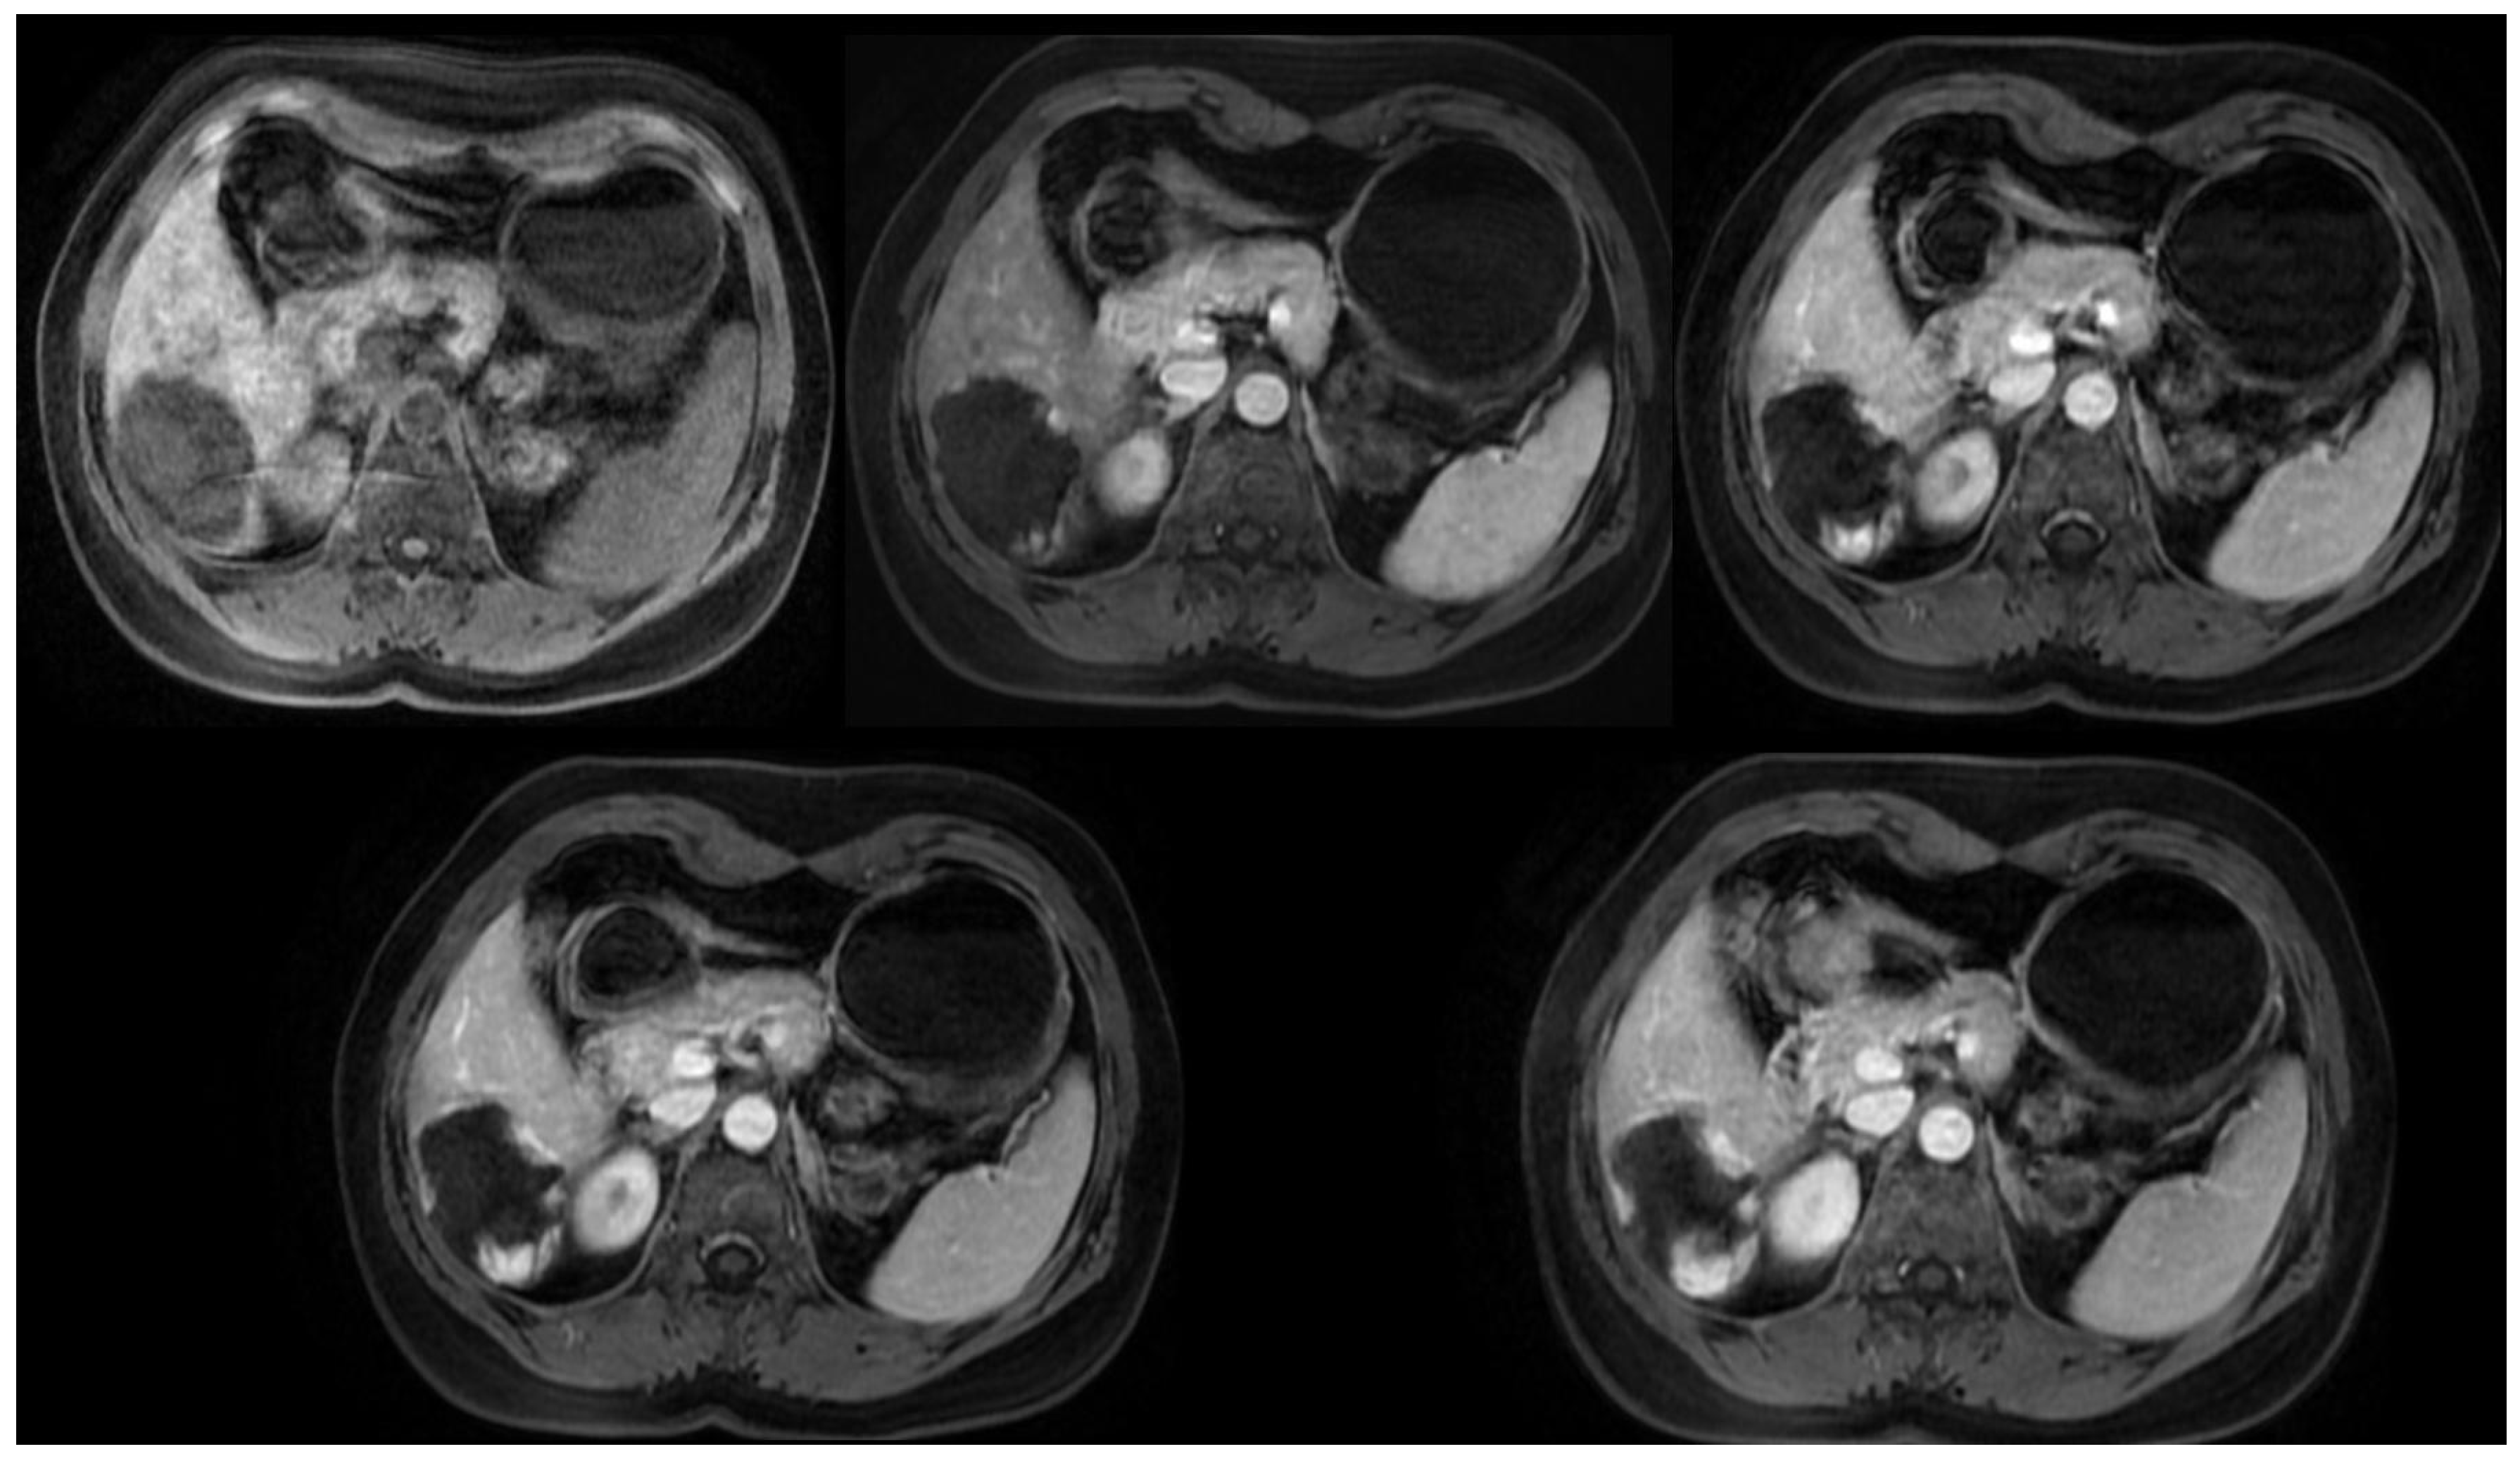

4.5. Magnetic Resonance Imaging

- McFarland, E.G.; Mayo-Smith, W.W.; Saini, S.; Hahn, P.F.; Goldberg, M.A.; Lee, M.J. Hepatic hemangiomas and malignant tumors: Improved differentiation with heavily T2-weighted conventional spin-echo MR imaging. Radiology 1994, 193, 43–47. [Google Scholar] [CrossRef] [PubMed]

- Chan, Y.L.; Lee, S.F.; Yu, S.C.H.; Lai, P.; Ching, A.S.C. Hepatic malignant tumour versus cavernous haemangioma: Differentiation on multiple breath-hold turbo spin-echo MRI sequences with different T2-weighting and T2-relaxation time measurements on a single slice multi-echo sequence. Clin. Radiol. 2002, 57, 250–257. [Google Scholar] [CrossRef] [PubMed]

- Tateyama, A.; Fukukura, Y.; Takumi, K.; Shindo, T.; Kumagae, Y.; Kamimura, K.; Nakajo, M. Gd-EOB-DTPA-enhanced magnetic resonance imaging features of hepatic hemangioma compared with enhanced computed tomography. World J. Gastroenterol. 2012, 18, 6269–6276. [Google Scholar] [CrossRef] [PubMed]

- Mamone, G.; Di Piazza, A.; Carollo, V.; Cannataci, C.; Cortis, K.; Bartolotta, T.V.; Miraglia, R. Imaging of hepatic hemangioma: From A to Z. Abdom. Radiol. 2020, 45, 672–691. [Google Scholar] [CrossRef] [PubMed]

- Caseiro-Alves, F.; Brito, J.; Araujo, A.E.; Belo-Soares, P.; Rodrigues, H.; Cipriano, A.; Sousa, D.; Mathieu, D. Liver haemangioma: Common and uncommon findings and how to improve the differential diagnosis. Eur. Radiol. 2007, 17, 1544–1554. [Google Scholar] [CrossRef] [PubMed]

- Mamone, G.; Miraglia, R. The “light bulb sign” in liver hemangioma. Abdom. Radiol. 2019, 44, 2327–2328. [Google Scholar] [CrossRef] [PubMed]

- Danet, I.M.; Semelka, R.C.; Braga, L.; Armao, D.; Woosley, J.T. Giant hemangioma of the liver: MR imaging characteristics in 24 patients. Magn. Reson. Imaging 2003, 21, 95–101. [Google Scholar] [CrossRef]